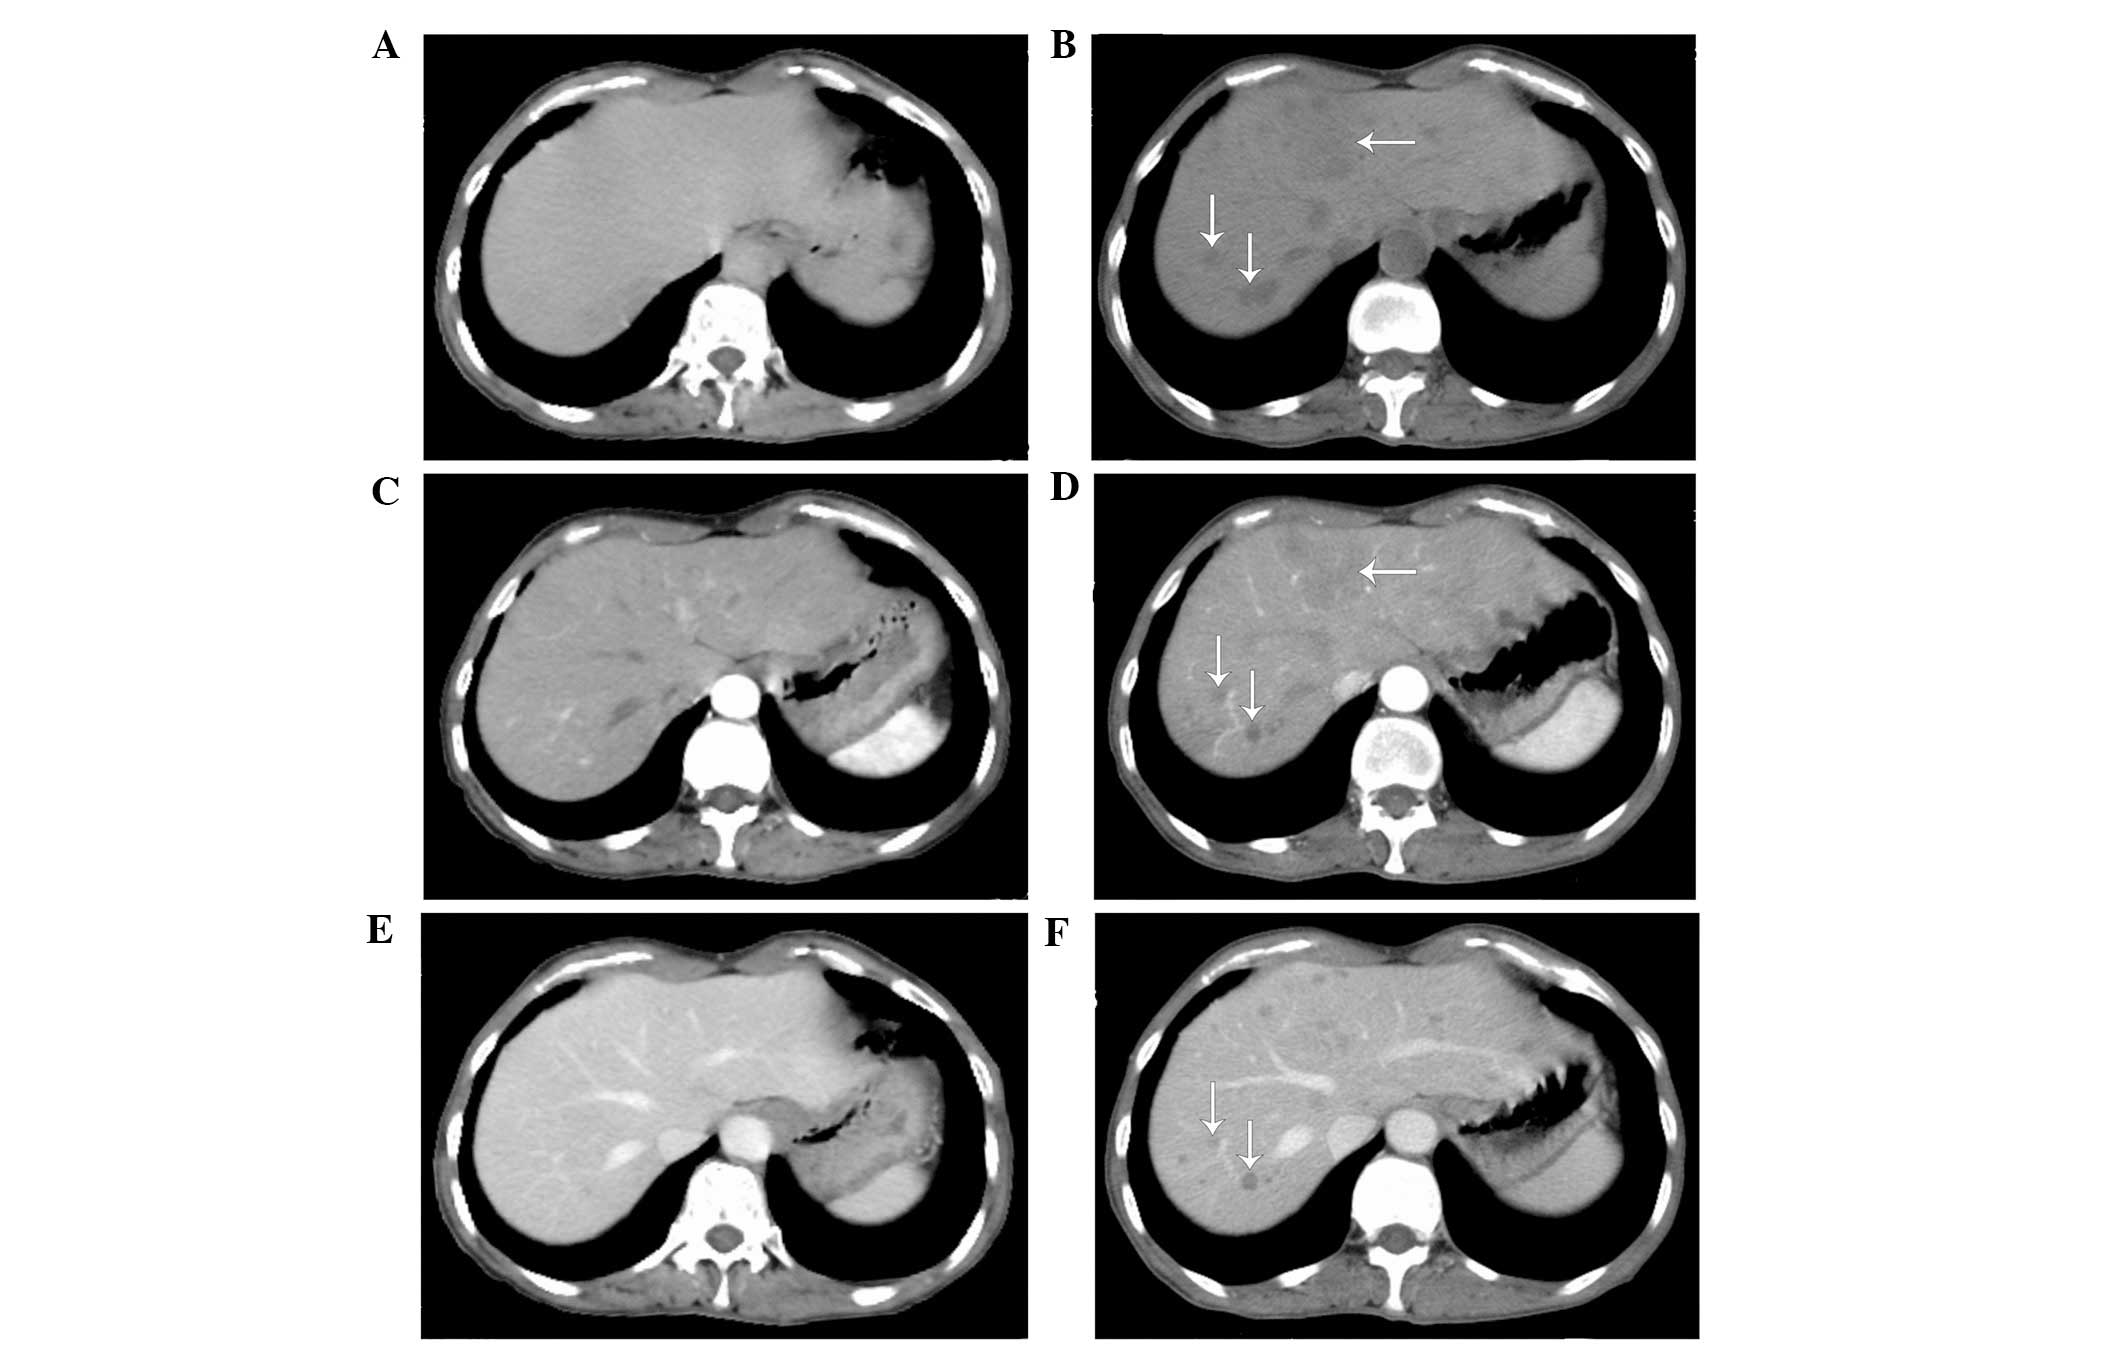

On March 10, 2014, a 62-year-old, non-smoking woman with an Eastern Cooperative Oncology Group Performance Status score of 2 (13) presented to the Department of Oncology, Comprehensive Cancer Center of Drum-Tower Hospital (Nanjing, China) with a cough that had been ongoing for 2 months. Computed tomography (CT; Discovery CT750 HD; GE Healthcare Life Sciences, Shanghai, China) revealed a primary mass in the left upper lobe of the lung (Fig. 1A and B), with multiple small pulmonary nodules (maximum diameter, 4 mm) observed bilaterally. A CT-guided fine needle aspiration biopsy of the primary lesion was performed on the left lung, which revealed the presence of a middle-differentiated adenocarcinoma. EGFR mutation analysis was performed on the biopsied tissue within exons 18 and 21. EGFR mutations were detected by amplification refractory mutation system in multiple quantitative polymerase chain reaction analysis with the Human EGFR Mutation Detection kit (YuanQi Bio-Pharmaceutical Co., Ltd., Shanghai, China), as previously described (14), which demonstrated a co-mutant of Del-19 (del 2239_2248+insC) and L858R. In addition, anaplastic lymphoma kinase rearrangement analysis was performed using fluorescence in situ hybridization, with negative results. The patient was orally administered erlotinib, at a dose of 150 mg/day. Two months later, no considerable relief of the cough was noted; however, a CT scan revealed that the primary lung mass had shrunk (Fig. 1C and D), but the bilateral multiple pulmonary nodules remained. In addition, prior to erlotinib treatment there was no hepatic metastases (Fig. 2A–C); however, following treatment multiple hepatic metastases were observed (Fig. 2D–F). Based on the Response Evaluation Criteria in Solid Tumors (RECIST) (15), the treatment response of the patient was assessed as progressive disease (PD). The patient refused to undergo a biopsy of the liver. Treatment with erlotinib was stopped when PD was detected, and 2 cycles (3 weeks/cycle) of chemotherapy with pemetrexed (500 mg/m2) plus cisplatin (75 mg/m2) were administered to the patient intravenously. However, the hepatic metastases continued to progress under the assessment of CT scans, which were performed monthly. The patient succumbed 2 months subsequent to the detection of PD, with the best supportive care possible. The patient's overall survival was ~5.3 months.

Figure 2.

Hepatic computed tomography scans. Absence of hepatic metastasis prior to erlotinib treatment was observed on a (A) plain, (B) venous phase and (C) arterial phase scan (arrows). Presence of hepatic metastasis following 8 weeks of erlotinib treatment was observed on a (D) plain, (E) venous phase and (F) arterial phase scan (arrows).

In the present case, the EGFR gene detection assay on the core biopsy tissue of the primary lesion in the left lung revealed Del-19 and L858R mutations. Notably, following the initiation of EGFR-TKI treatment the primary lung mass shrunk and hepatic metastases appeared extensively. The present study hypothesizes that the genomic features of the hepatic metastases varied from those of the primary tumor, indicating that intertumor heterogeneity may be responsible for the PD observed in the present patient. In addition, de Bruin et al (29) revealed evidence of branched evolution with driver mutations arising prior to and following subclonal diversification, which supports the hypothesis of the present authors. Considering that the majority of NSCLC driver mutations occur in the early phases of tumor evolution (29), the Del-19 + L858R mutations of the present patient may have been truncal mutations of the ancestral clone, existing only in the primary lung lesion. With regard to the hepatic metastases, it is likely that they consisted of sectional and predominant subclones with branch gene alternations that confer de novo resistance to EGFR-TKIs, including phosphatidylinositol-4,5-bisphosphate 3-kinase catalytic subunit α, phosphatase and tensin homolog, protein kinase B and serine/threonine kinase 11 alterations, c-met amplification, hepatocyte growth factor overexpression and Kirsten ras mutations (30–34). Under circumstances when re-biopsy is not feasible, comprehensive genomic detection and multi-targeted therapies may be used. It has been suggested that liquid biopsy may reveal relatively comprehensive gene alternations and provide predictive information on the identification of therapeutic targets and resistance mechanisms (35).